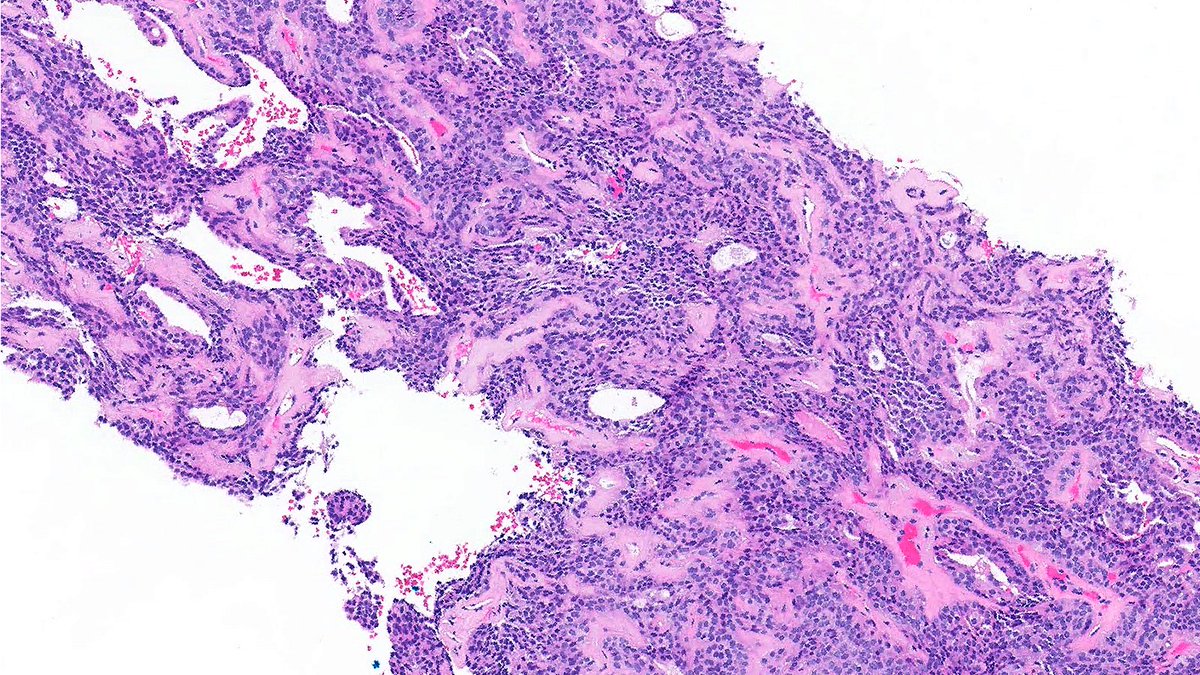

Soft tissue nodule. Can you diagnose it from one pic, or is it #TooLowToDiagnose? Answer ✅ youtu.be/EPyakVOCmFs?si… Digital slide: kikoxp.com/posts/51103 #pathology #pathTwitter #dermpath #dermatology #parasitology #dermatologia #dermtwitter

Soft tissue nodule. Can you diagnose it from one pic, or is it #TooLowToDiagnose?

Answer ✅ youtu.be/EPyakVOCmFs?si…

Digital slide: kikoxp.com/posts/51103